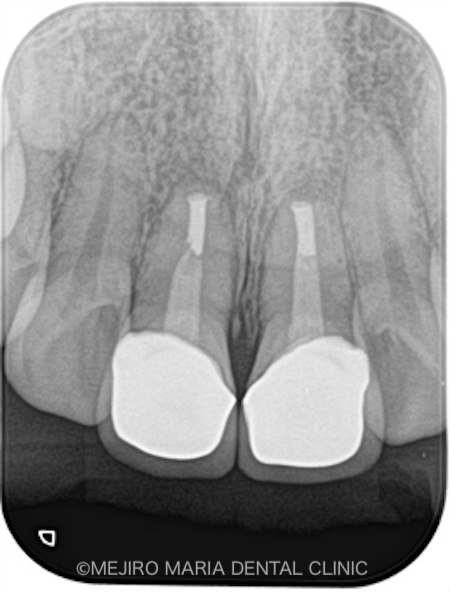

|レントゲン画像_治療前3-1.png)

本症例の患者様は、2年前に交通事故で前歯を負傷しました。その際近隣の歯科医院で前歯2本を抜髄し、オールセラミッククラウンを装着されました。しかし、右上の1番はセラミック装着後すぐにろう孔が出現し同時に違和感を覚えるようになったため、治療を行った歯科医院に相談した結果、歯根端切除術を行ったとのことでした。

ところが歯根端切除術を施すも、根尖部の腫脹が改善されなかったため、当院に来院されました(1枚目写真の矢印)。

初診時にCT撮影を行い診査したところ、右上1番の根尖の骨は、根尖性歯周炎により喪失していました。また、左上1番の歯にも小さい病変(根尖性歯周炎)が確認されました(2枚目の写真)。